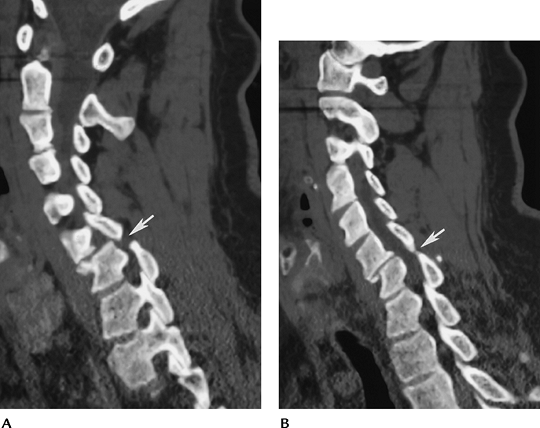

P.82

![]() |

|

FIGURE 3-41 Sagittal reformatted CT images (A, B) of bilateral pars defects (arrow).